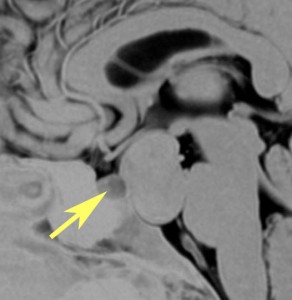

下垂体柄の周囲にのう胞性腫瘍があります。T1強調画像では等信号,T2強調画像ではまだらな信号になっています。23年という長い経過から液状内容物が固形化したものと推定されます。T2で低信号となる部分があるのですが,黄色肉芽腫とは異なる像です。

下垂体柄は長く伸びています。のう胞による長期の圧迫のため斜台上部がerosionになって凹んでいます。トルコ鞍内の中間葉の位置に典型的な小さなラトケのう胞(黄色矢印)がみられますが,これは長年変化していませんでした。

左前頭側頭開頭 pterional approachで,のう胞壁を含めて完全摘出 complete removalしました。のう胞は下垂体柄の左側に付着してそこから発生したものでした。内容物は固体で寒天状のコロイドでした,一部軟らかくて一部は線維化していました。のう胞壁は半透明で薄い部分も線維性の膜状の部分もありました。病理検査では上皮細胞が証明されて内胚葉のう胞 endodermal cystの診断です。

ラトケのう胞はhiatusから内容液吸引だけして,皮膜はもちろんそのままにしています。